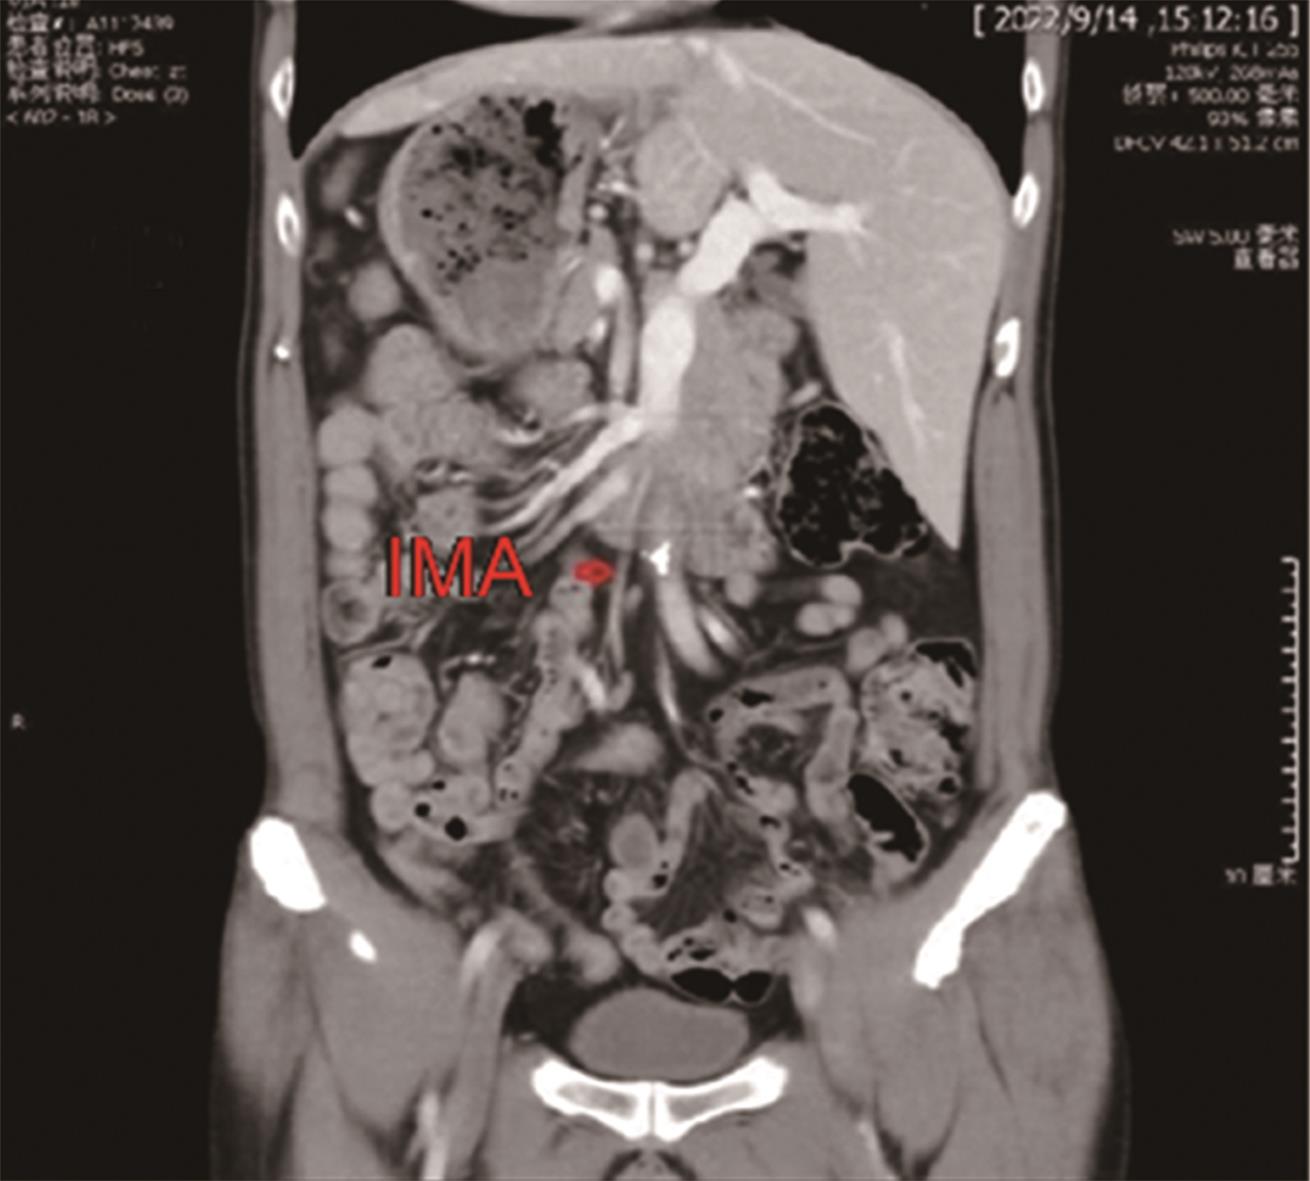

• “镜面人”保留左结肠动脉腹腔镜低位直肠癌根治术1例

2023, 48(7):853-856. DOI: 10.13406/j.cnki.cyxb.003278

摘要 (87) HTML (56) PDF 3.64 M (283) 评论 (0) 收藏